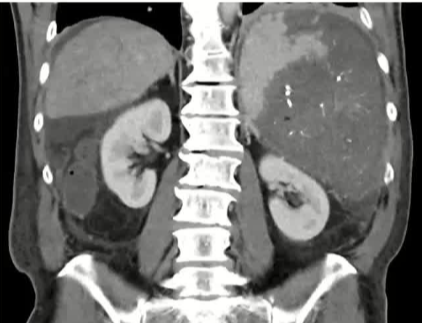

栓塞材料的可及性(例如病灶栓塞材料的可到达性)accessability (e.g. reachability of the nidus) 栓塞的预期深度intended deepness of embolization 如果需要让栓塞填满最后1mm 预期效果(例如:门静脉栓塞的炎症)intended effect (e.g. inflammation in PVE) 凝血状态(达到止血效果所需的时间)coagulation state (duration until hemostasis) 并发症(过敏、心律不齐、肺动脉高压、肝纤维化等)comorbidities (allergies, arrythmia, pulmonary hypertension, lung fibrosis etc.) 处于危险中的结构(包括下游部分-downstream和反流部分) structures at risk (downstream & backwash) 靶病变定位(浅层与深层) target lesion localization (superficial vs. deep) 不会选择一些会引起炎症的东西,因为那会病人来说真的很痛苦浅层病变 栓塞所需的速度(例如:危及生命的出血情况)required speed of embolization (e.g. life threatening hemorraghe) 院外专业人员(DSA技术人员和介入放射科医生)local expertise (technicians & IR's) 可用性与定价 availabilty & pricing Patient assessment for the choice of the ideal liquid emboli 影像学 62岁 男性